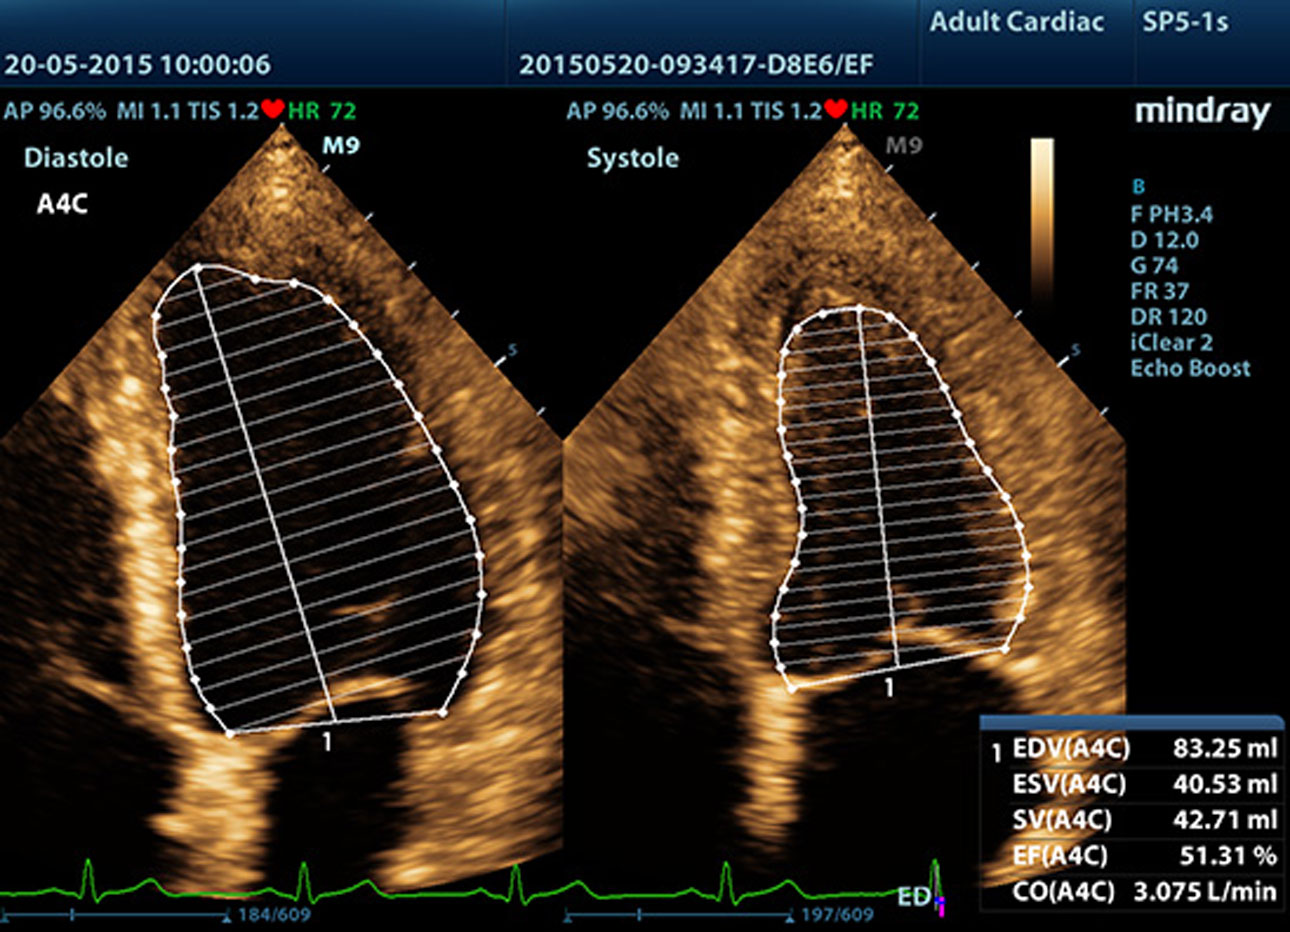

AutoEF

Intelligent way to analyze 2D echo clips to automatically recognize diastole/systole frames and output EDV/ESV/EF etc. results by Simpson method.